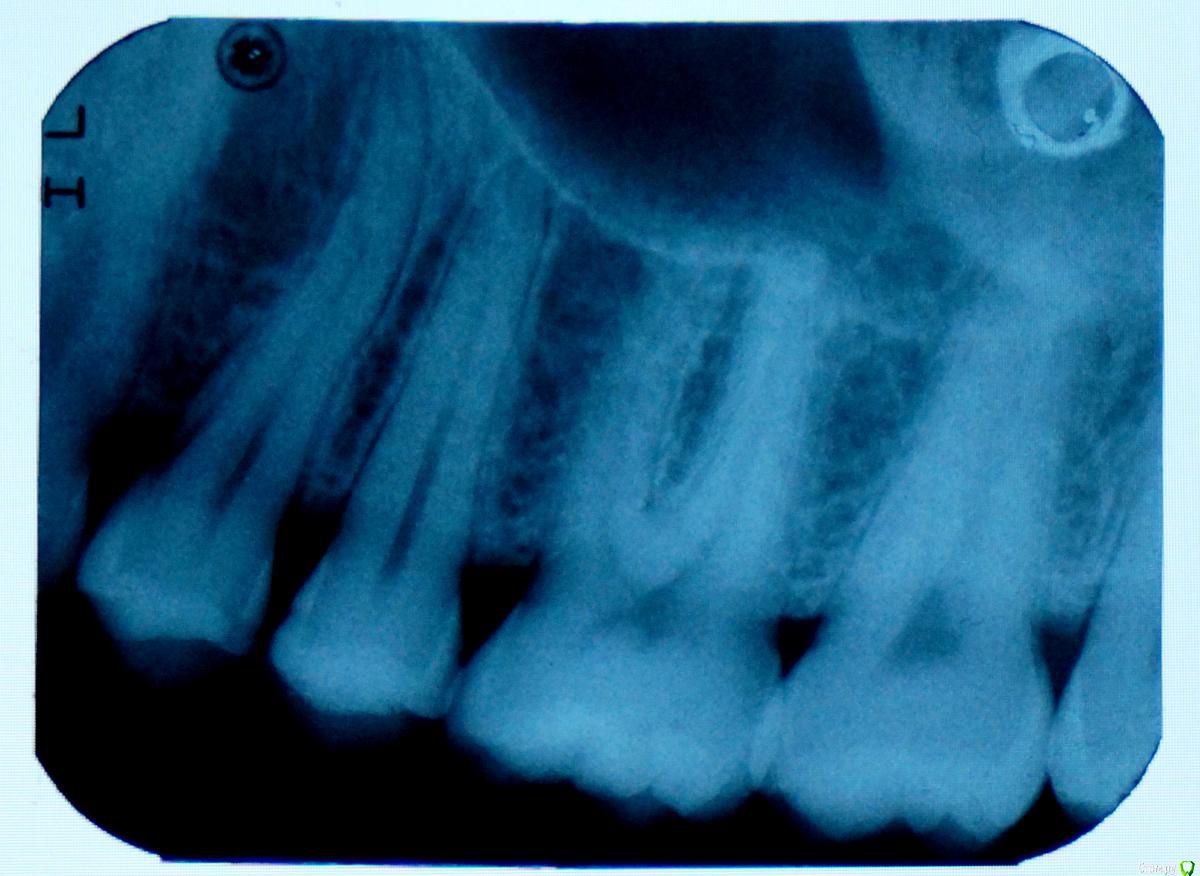

Манул Опубликовано 10 сентября, 2015 Поделиться Опубликовано 10 сентября, 2015 Здравствуйте. У меня боль в суставе челюстном слева, глаз отекает (мешок с утра). И при жевании боль в 6 зубе верхнем слева (если считать от центрального резца). Сделал панорамный, на нем всё нормально? Что делать, что может быть? Спасибо. Ссылка на комментарий

krokomot Опубликовано 10 сентября, 2015 Поделиться Опубликовано 10 сентября, 2015 По вашему снимку видимой патологии не наблюдается, нужно обратиться непосредственно на прием, если беспокоят зубы проверить их на витальность. Это все можно сделать только в клинике форум вам тут не поможет все будет только пальцем в небо. Ссылка на комментарий

Манул Опубликовано 11 сентября, 2015 Автор Поделиться Опубликовано 11 сентября, 2015 По вашему снимку видимой патологии не наблюдается, нужно обратиться непосредственно на прием, если беспокоят зубы проверить их на витальность. Это все можно сделать только в клинике форум вам тут не поможет все будет только пальцем в небо.Проблема в том, что зубы все интактны (стучали и воздушной струей проверяли), я у многих врачей был у 3 хирургов, 5 парадонтологов, 2 терапевтов..."У вас всё в норме!"А боль не проходит, есть не могу и глаз отекает (как фингал под глазом небольшой).Окулист сказа его патологии нет, у ЛОРа пока не был, но заложенности носа нет...Я не знаю что делать, всё в норме, а всё болит. Я не могу сказать, что идет усиление боли со временем, но и не проходит ничего. Ссылка на комментарий

Манул Опубликовано 22 сентября, 2015 Автор Поделиться Опубликовано 22 сентября, 2015 Спасибо всем огромное! По зависящим от меня причинам, я вынужденно исчез. С вычислительной техникой проблемы случились...На зубах кариес межзубной начался на стороне где болело. (между пятым, шестым и четвертым зубами)Подскажите стоит пломбировать или подожать нужно.Пишу с Raspberry pi b model 1... ((( Спасибо! Ссылка на комментарий